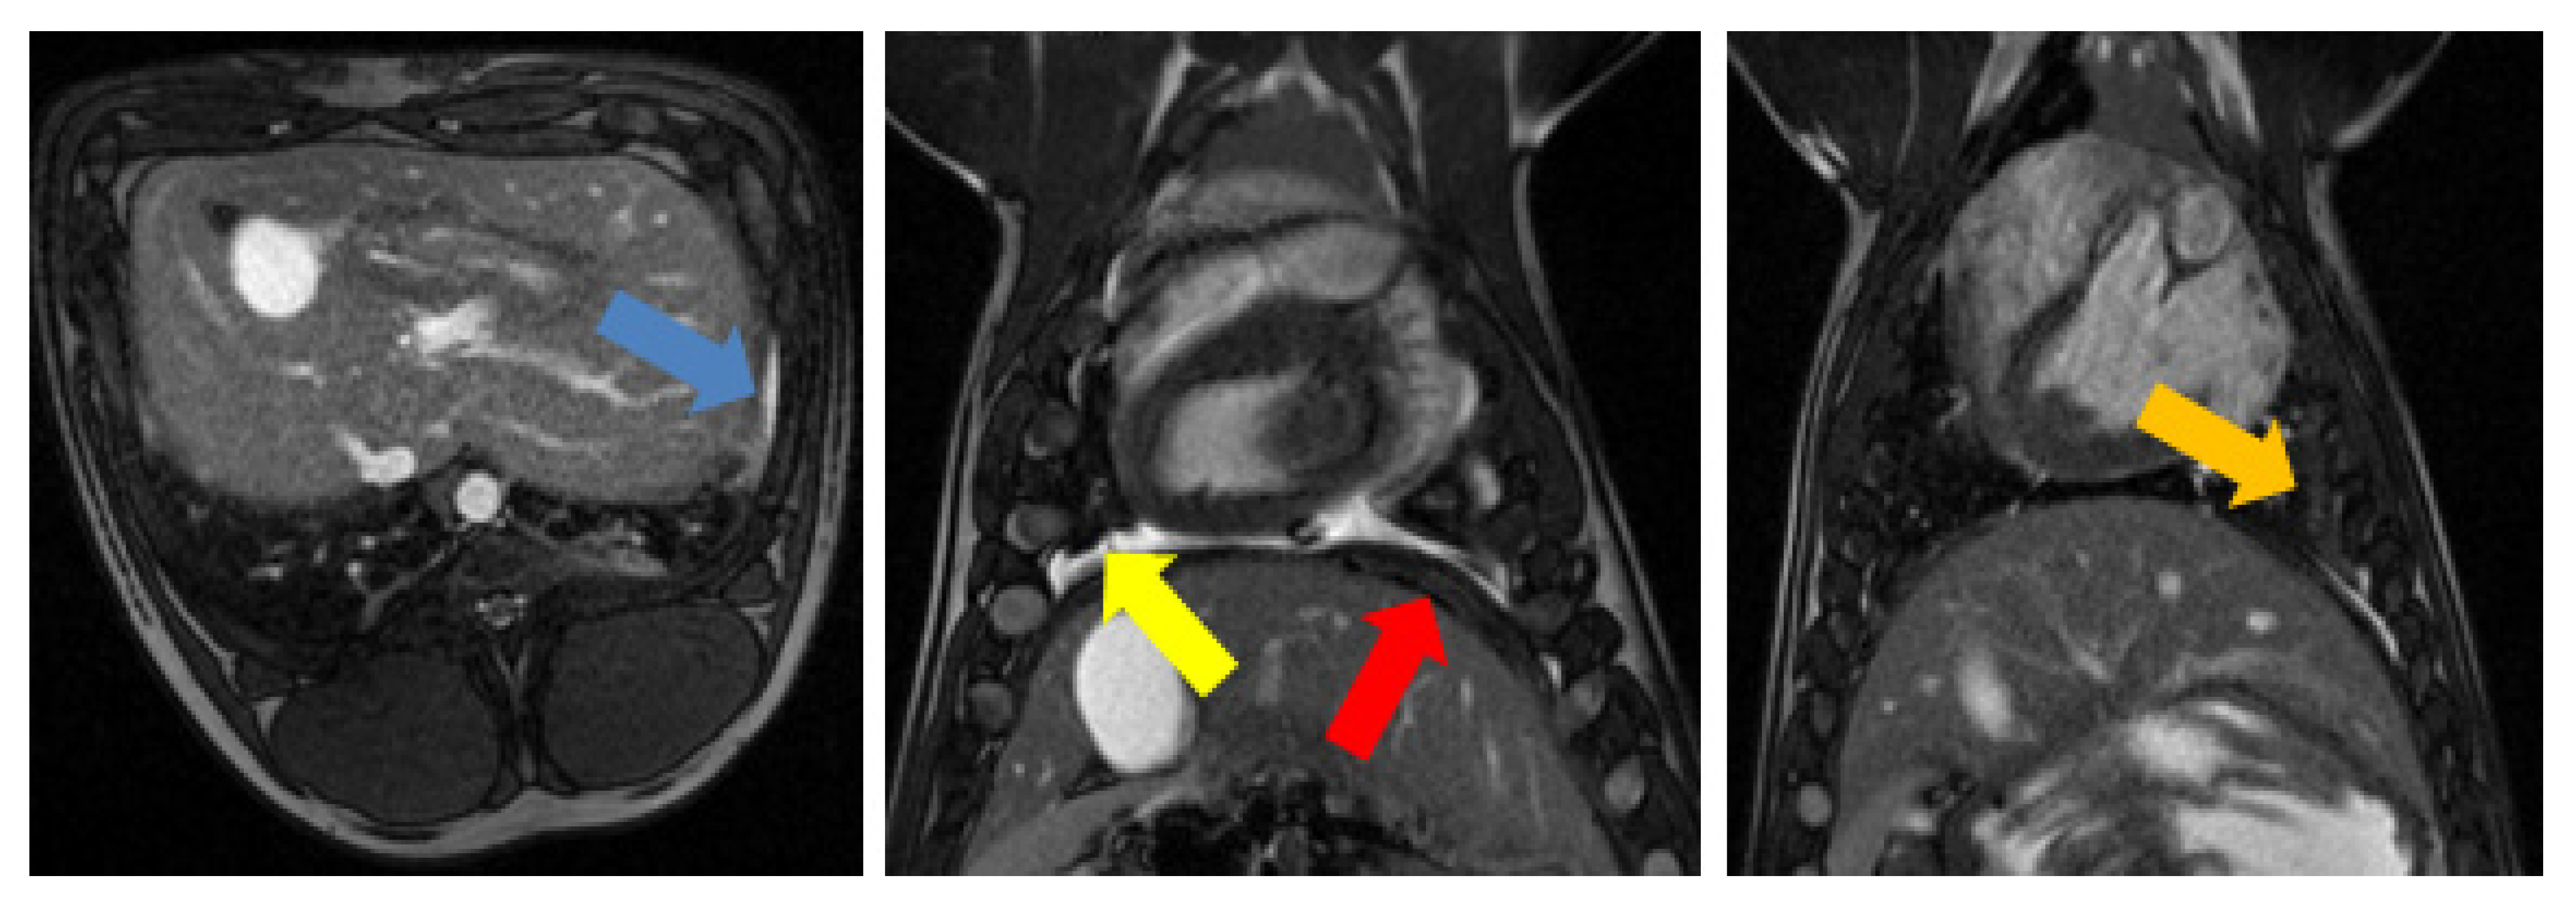

3.1. Tumor Model

3.2. Radiofrequency Ablation

3.3. Magnetic-Resonance-Guided Focused Ultrasound